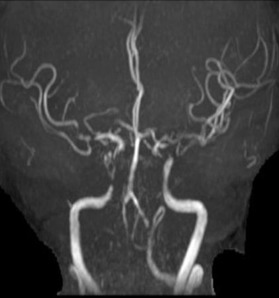

MRA

重要影像结论:左侧基底节区、放射冠区新发脑梗死;多发脑血管狭窄

头颅核磁:颅内多发缺血灶;DWI未见明显高信号;灌注可见右侧半球低灌注

头颅MRA:右侧椎动脉闭塞可能,双侧颈内动脉末端、左侧椎动脉V4段重度狭窄可能。